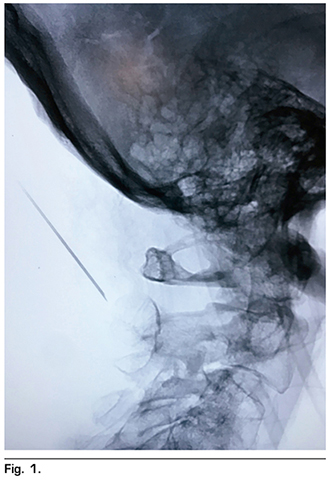

Figura 1